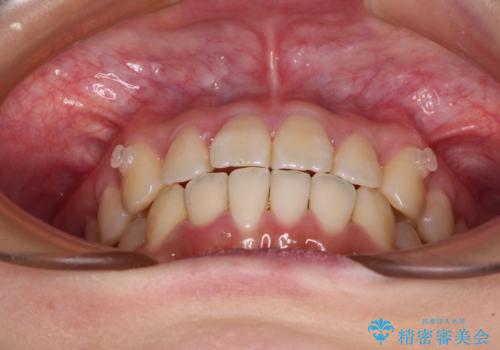

- 前歯の捻れを気にして来院された患者様です。

上顎前歯が捻れて前方に飛び出しており、下顎前歯もそれに沿うようにデコボコとなっていました。

IPR(歯と歯の間を削る処置)によりスペースを獲得して下顎前歯のデコボコを改善し、上顎前歯は下顎前歯と接する位置にまで引っ込めるように設定し、インビザラインにて矯正治療を行うこととしました。

しっかりと装着時間を守ってくださったので、予定通り1年強で治療を終えることができました。